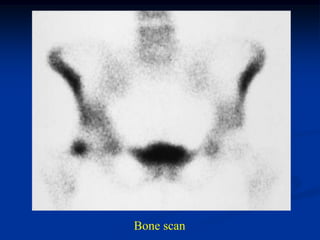

Case #1147             Metastatic Lung

46 year male with central fracture dislocation thru metastatic

lung CA of left peri-acetabular area